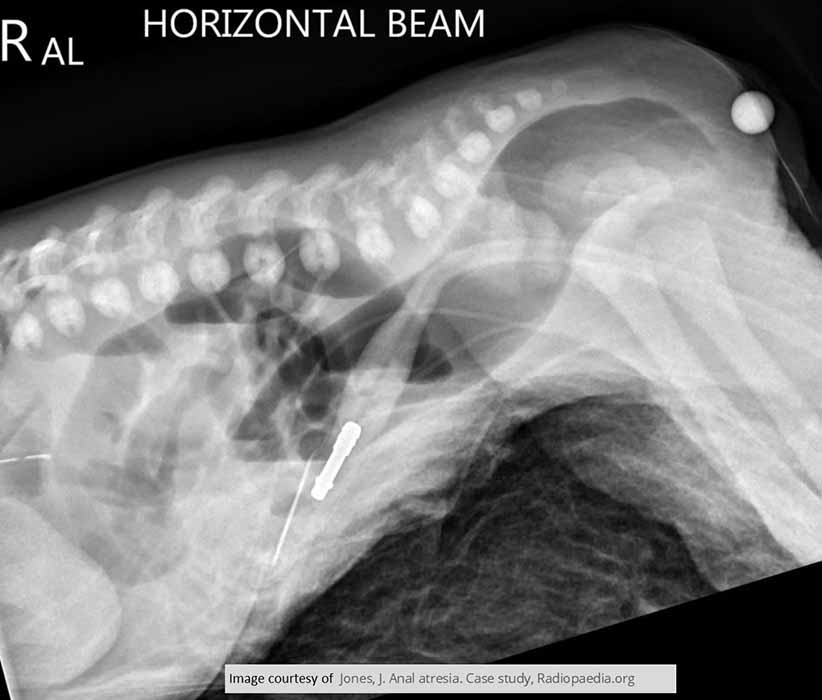

What is imperforate anus?

A congenital failure of the membrane between the rectum and anus to rupture.

What other names are used for imperforate anus?

Anal agenesis and rectal atresia.

Why does bowel obstruction occur in imperforate anus?

The rectum does not communicate with the anus.

How is imperforate anus categorized anatomically?

As high or low, depending on distance from the anus.

What associated abnormalities are common with imperforate anus?

Genitourinary fistulas.

What is the earliest sign of imperforate anus?

Failure to pass meconium. (babies first stool)

What additional signs may be present with imperforate anus?

Abdominal distension and stool in urine or vagina.

How is imperforate anus treated?

Surgical correction and fistula repair.